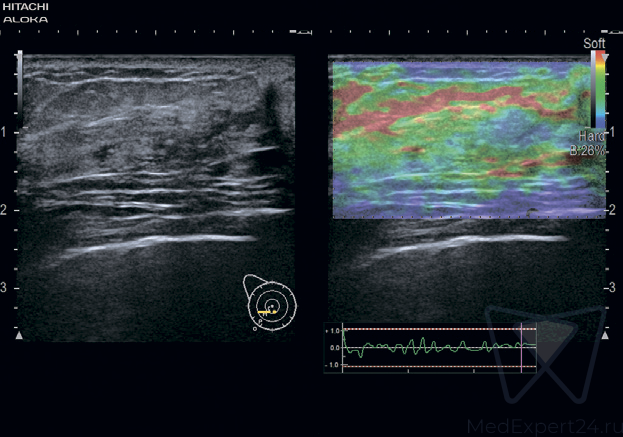

- FMD исследование поток-опосредованной дилатации артерий для ранней и точной диагностики атеросклероза,

- eTracking оценка эластичности стенки артерии для ранней диагностики атеросклероза,